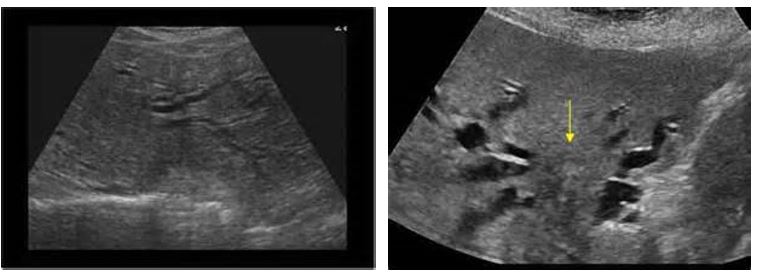

Distension (hydrops) of the gallbladder but showing what?

sludge with hydrops

4 pics of Choledochal Cysts

Transverse and longitudinal scan of a young patient with a choledochal cyst (Ccy) in the right upper quadrant.

Localized cystic dilation of the common bile duct

Diverticulum from the common bile duct

Invagination of the common bile duct into the duodenum

Dilation of the entire common bile duct and the common hepatic duct